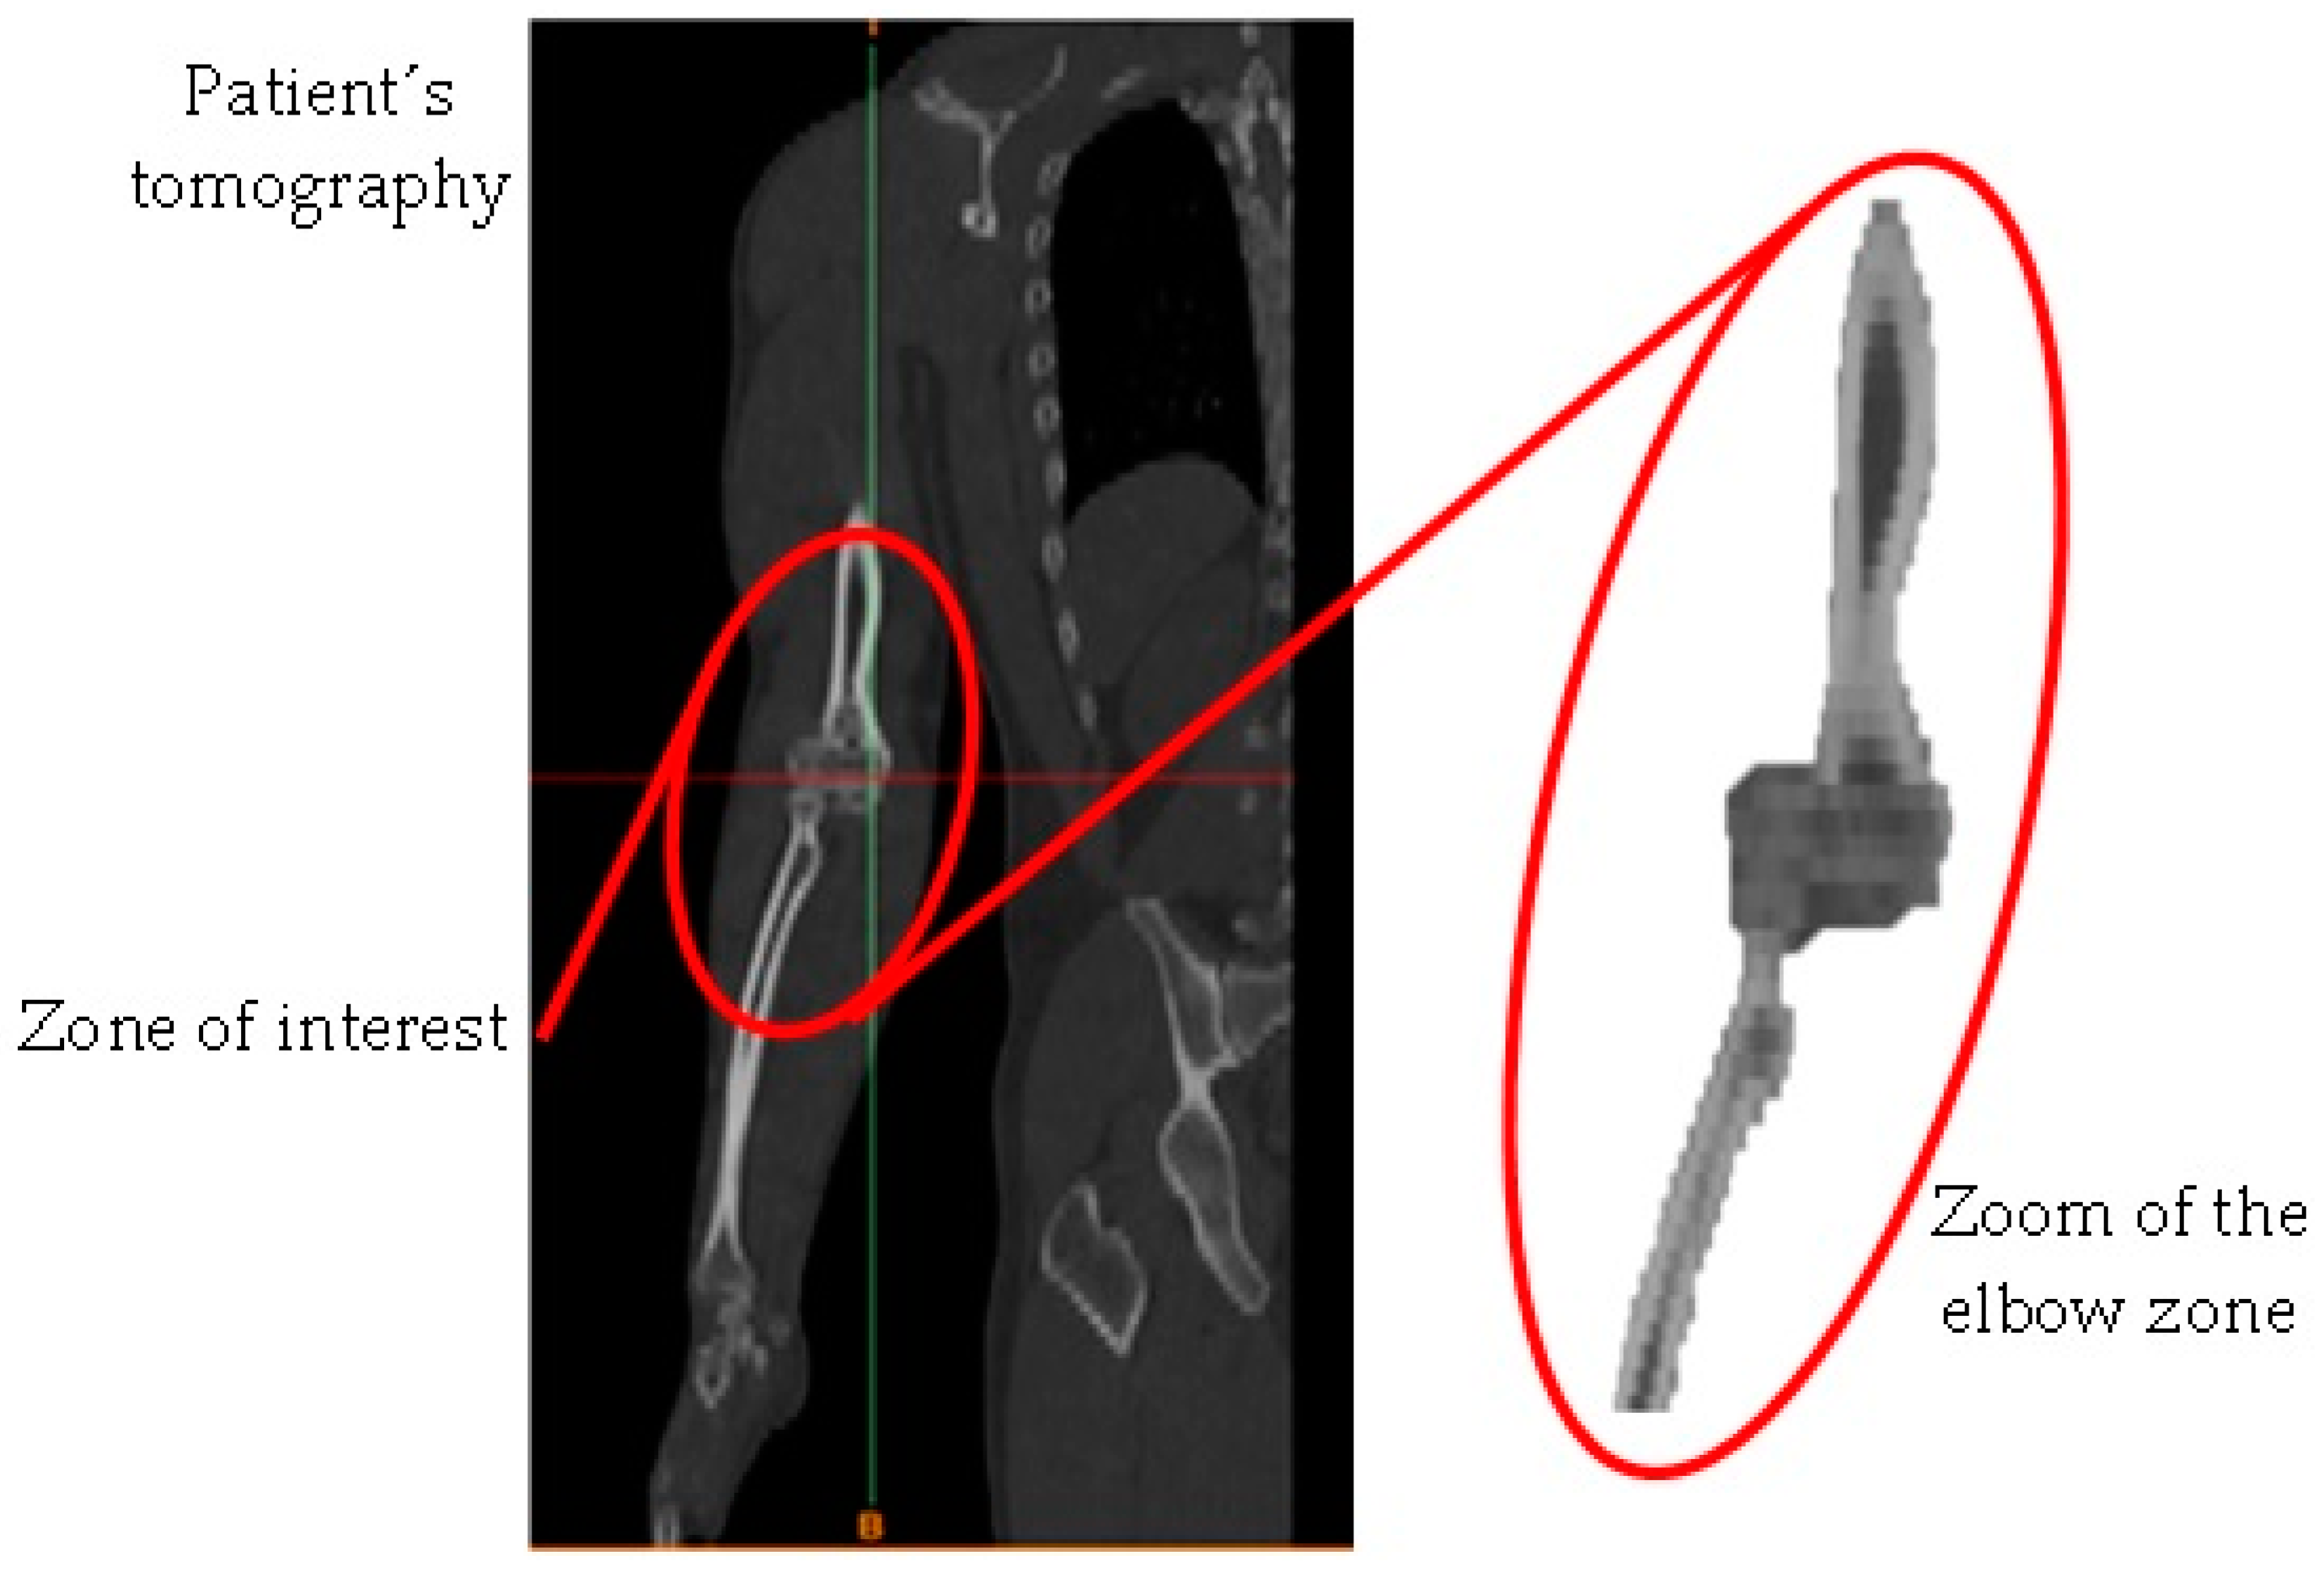

The methodology to develop a biomodel derives from a series of steps that involve computerized tomography in the DICOM format. For this study case, a computerized tomography scan of half of the patient’s torso was performed, where the working area to be characterized was enclosed (Figure 1) and included the elbow bones (humerus–radius–ulna), cartilage, and ligaments (Figure 2) [13]. Initially, the files obtained were imported into a computer program that can read the format. Next, a workspace was opened, consisting of four views (coronal, sagittal, axial, and total visualization of the model) where the slices that make up the tomography could be seen (Figure 3). It is possible to delimit the working area, and the software can automatically differentiate biological tissues. For this biomodel, a density mask range selection had a minimum value of 226 and a maximum value of 3071. The computational program can delimit the contour of the area of interest (Figure 4) without exceeding the established thickness (in this case, the cortical bone of the humerus, radius, and ulna). For trabecular bone, the density mask range was produced by an automatic procedure (cavity fill command), which identifies the cavity in the cortical bone and fills the space with soft material. However, the ligaments cannot be seen in computerized tomography, so ligaments were introduced in the biomodel by filling material in the space where the biological tissue is missing, which must be carried out manually (although the ligaments may present structural contact mismatch due to the complex shape or thickness of the structure) (Figure 5). Biomodel errors or mismatches are modified using reduction and smoothing commands for the component until the desired biological shape is correct. When generating contact between cortical bone and ligament, the most common thing that occurs is elements overlapping, which is resolved by performing a Boolean operation (removing the excess in material) and generating a uniformly smooth contact. Once the process has finished for each of the layers, the biomodel is operational and can be observed in the design window (Figure 6).

Figure 1. Patient’s tomography.